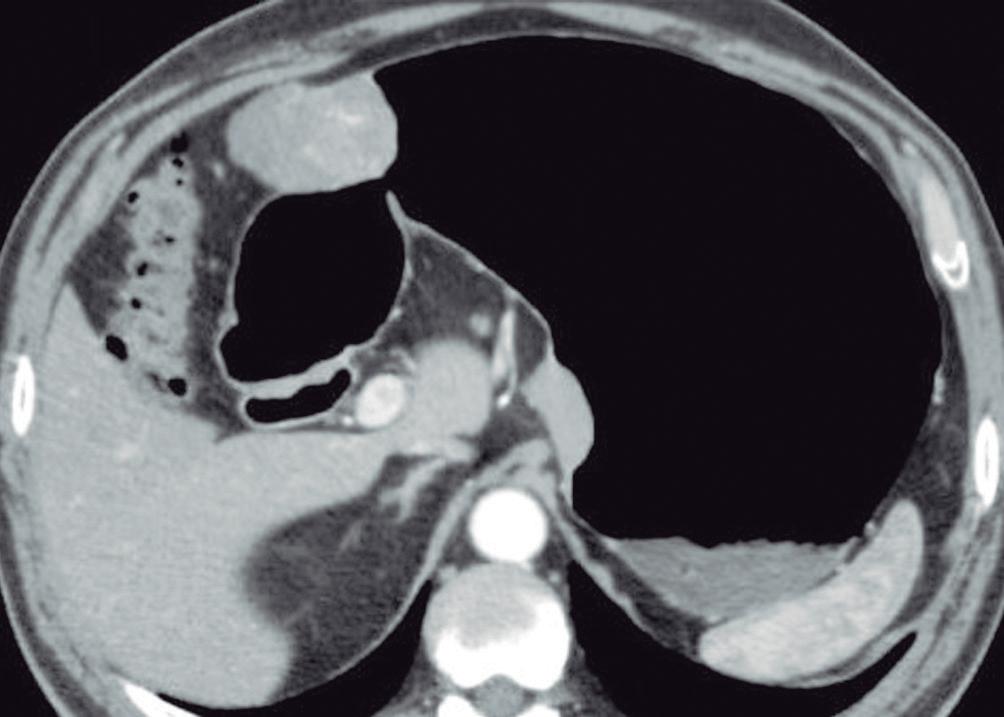

Evaluación de un paciente con dolor epigástrico y hallazgos sincrónicos infrecuentes

Roy López Grove, Daniela Soloaga, Juan Carlos Spina

Roy López Grove, Daniela Soloaga, Juan Carlos Spina 398